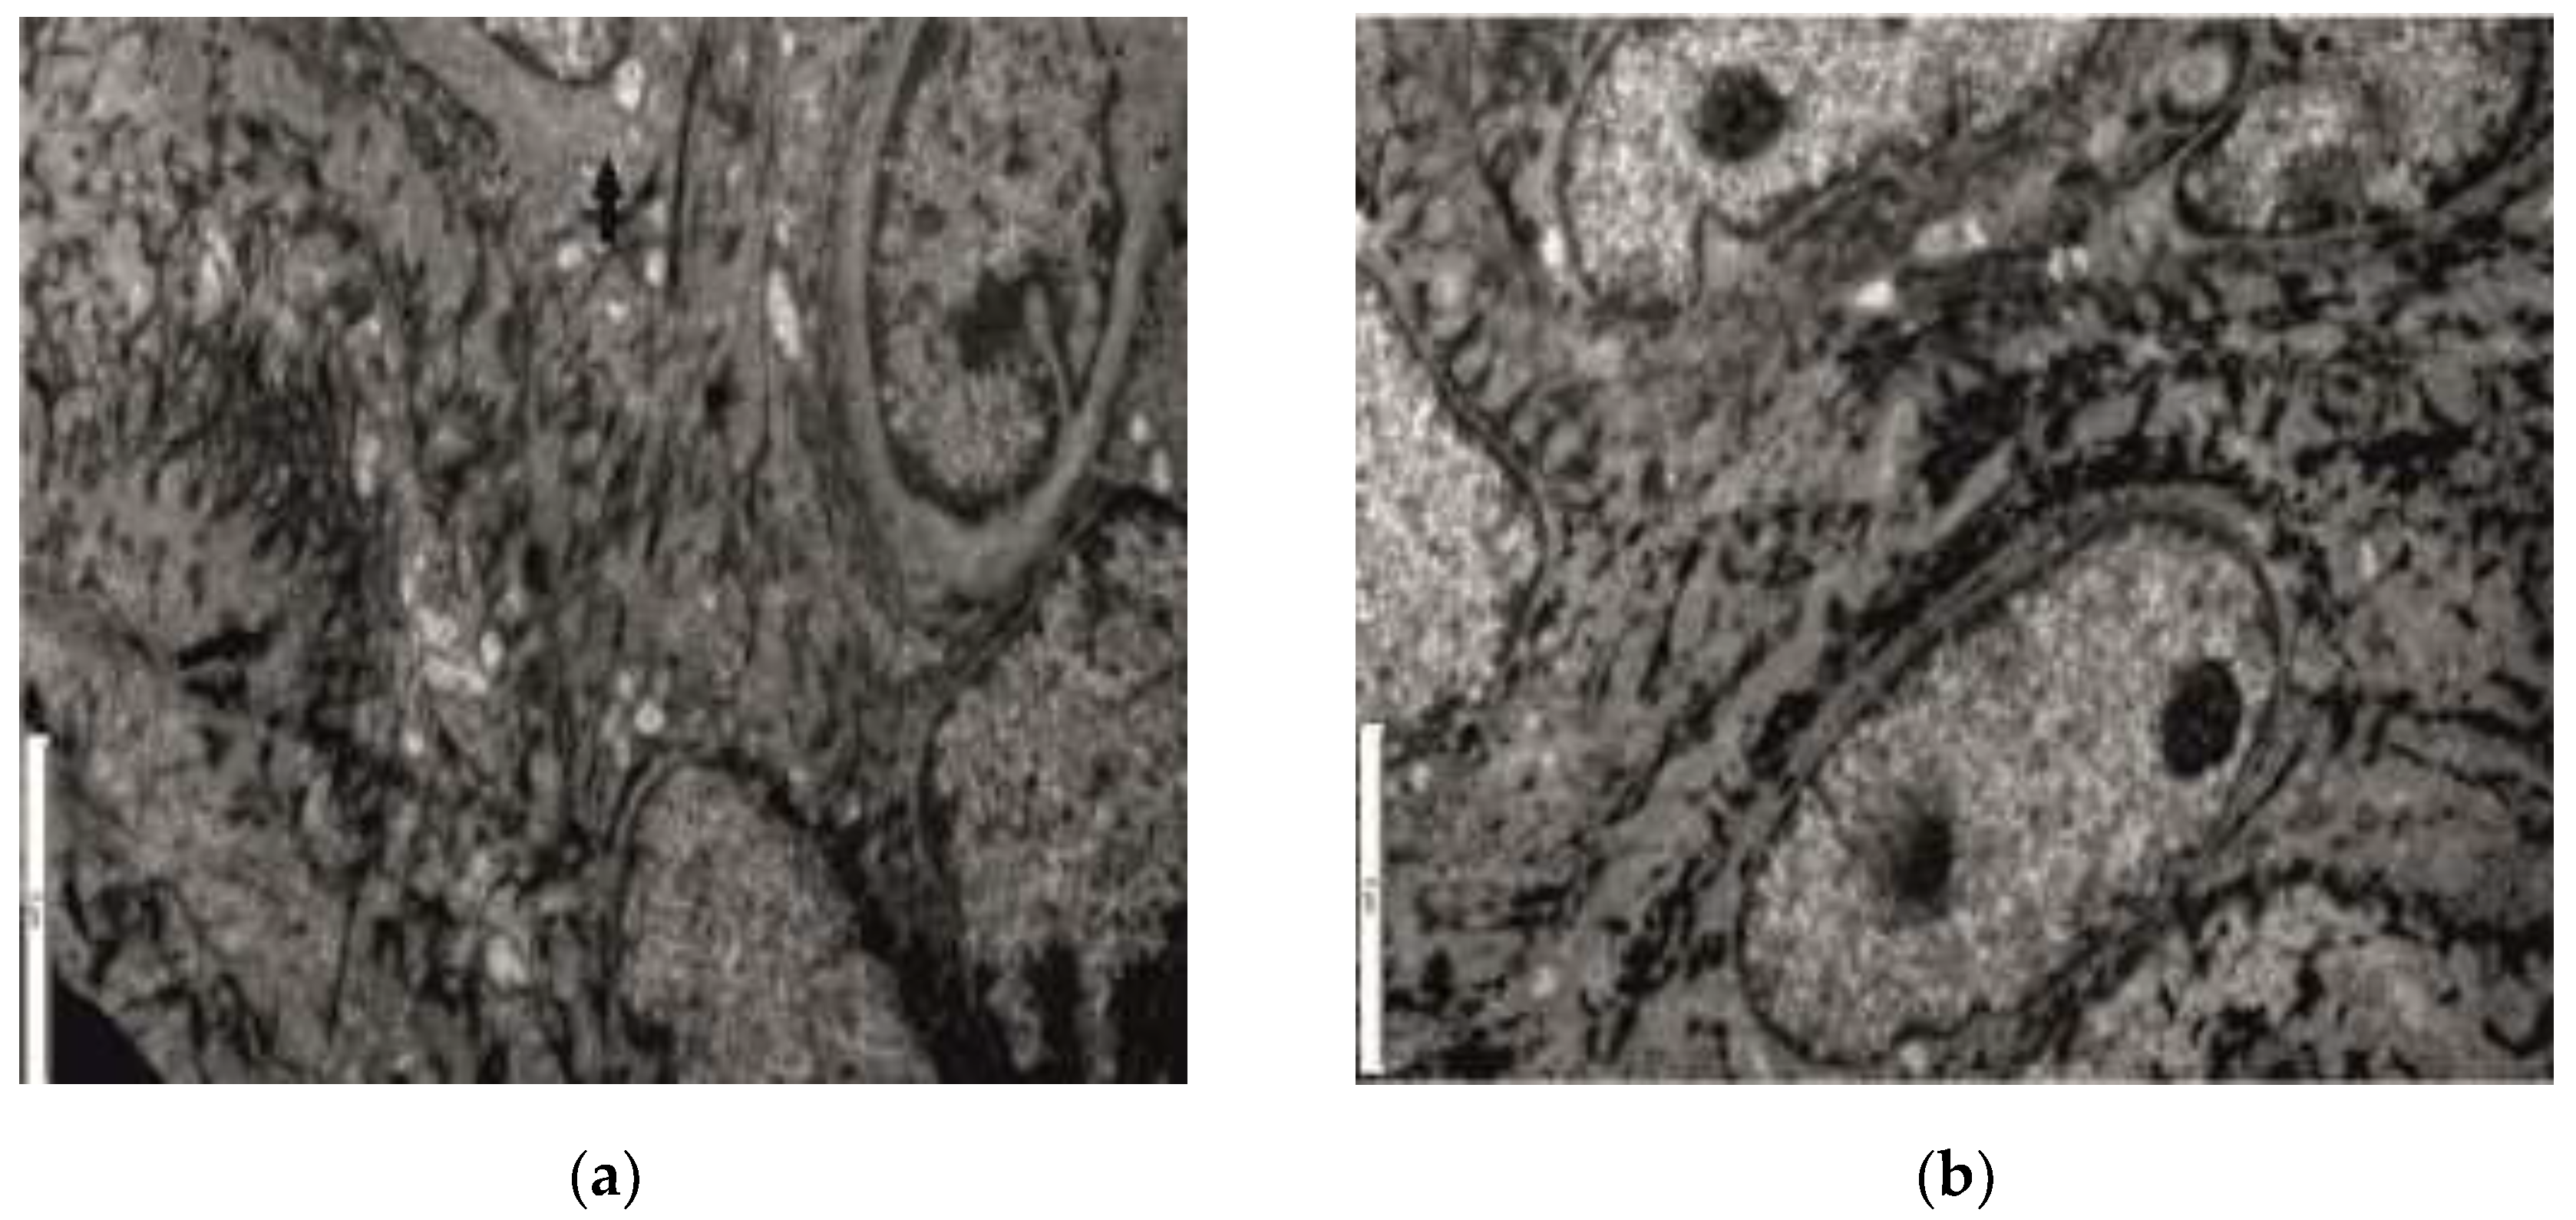

3.2. Ultrastructural Aspects

| Experimental diabetes mellitus(n = 36) | P palues forChi square testLikelihood Ratio | |

|---|---|---|

| vascularendothelium (n) | capillary level (32) | |

| 0.137 | ||

| metarteriolar level (26) | ||

| junctional complexes (n) | desmosomes (25) | 0.802 |

| basement membrane (23) | ||

| cellular organelles (n) | ||

| mitochondrial structure (35) | ||

| rough endoplasmic reticulum (30) | 0.201 | |

| Golgi apparatus (31) |